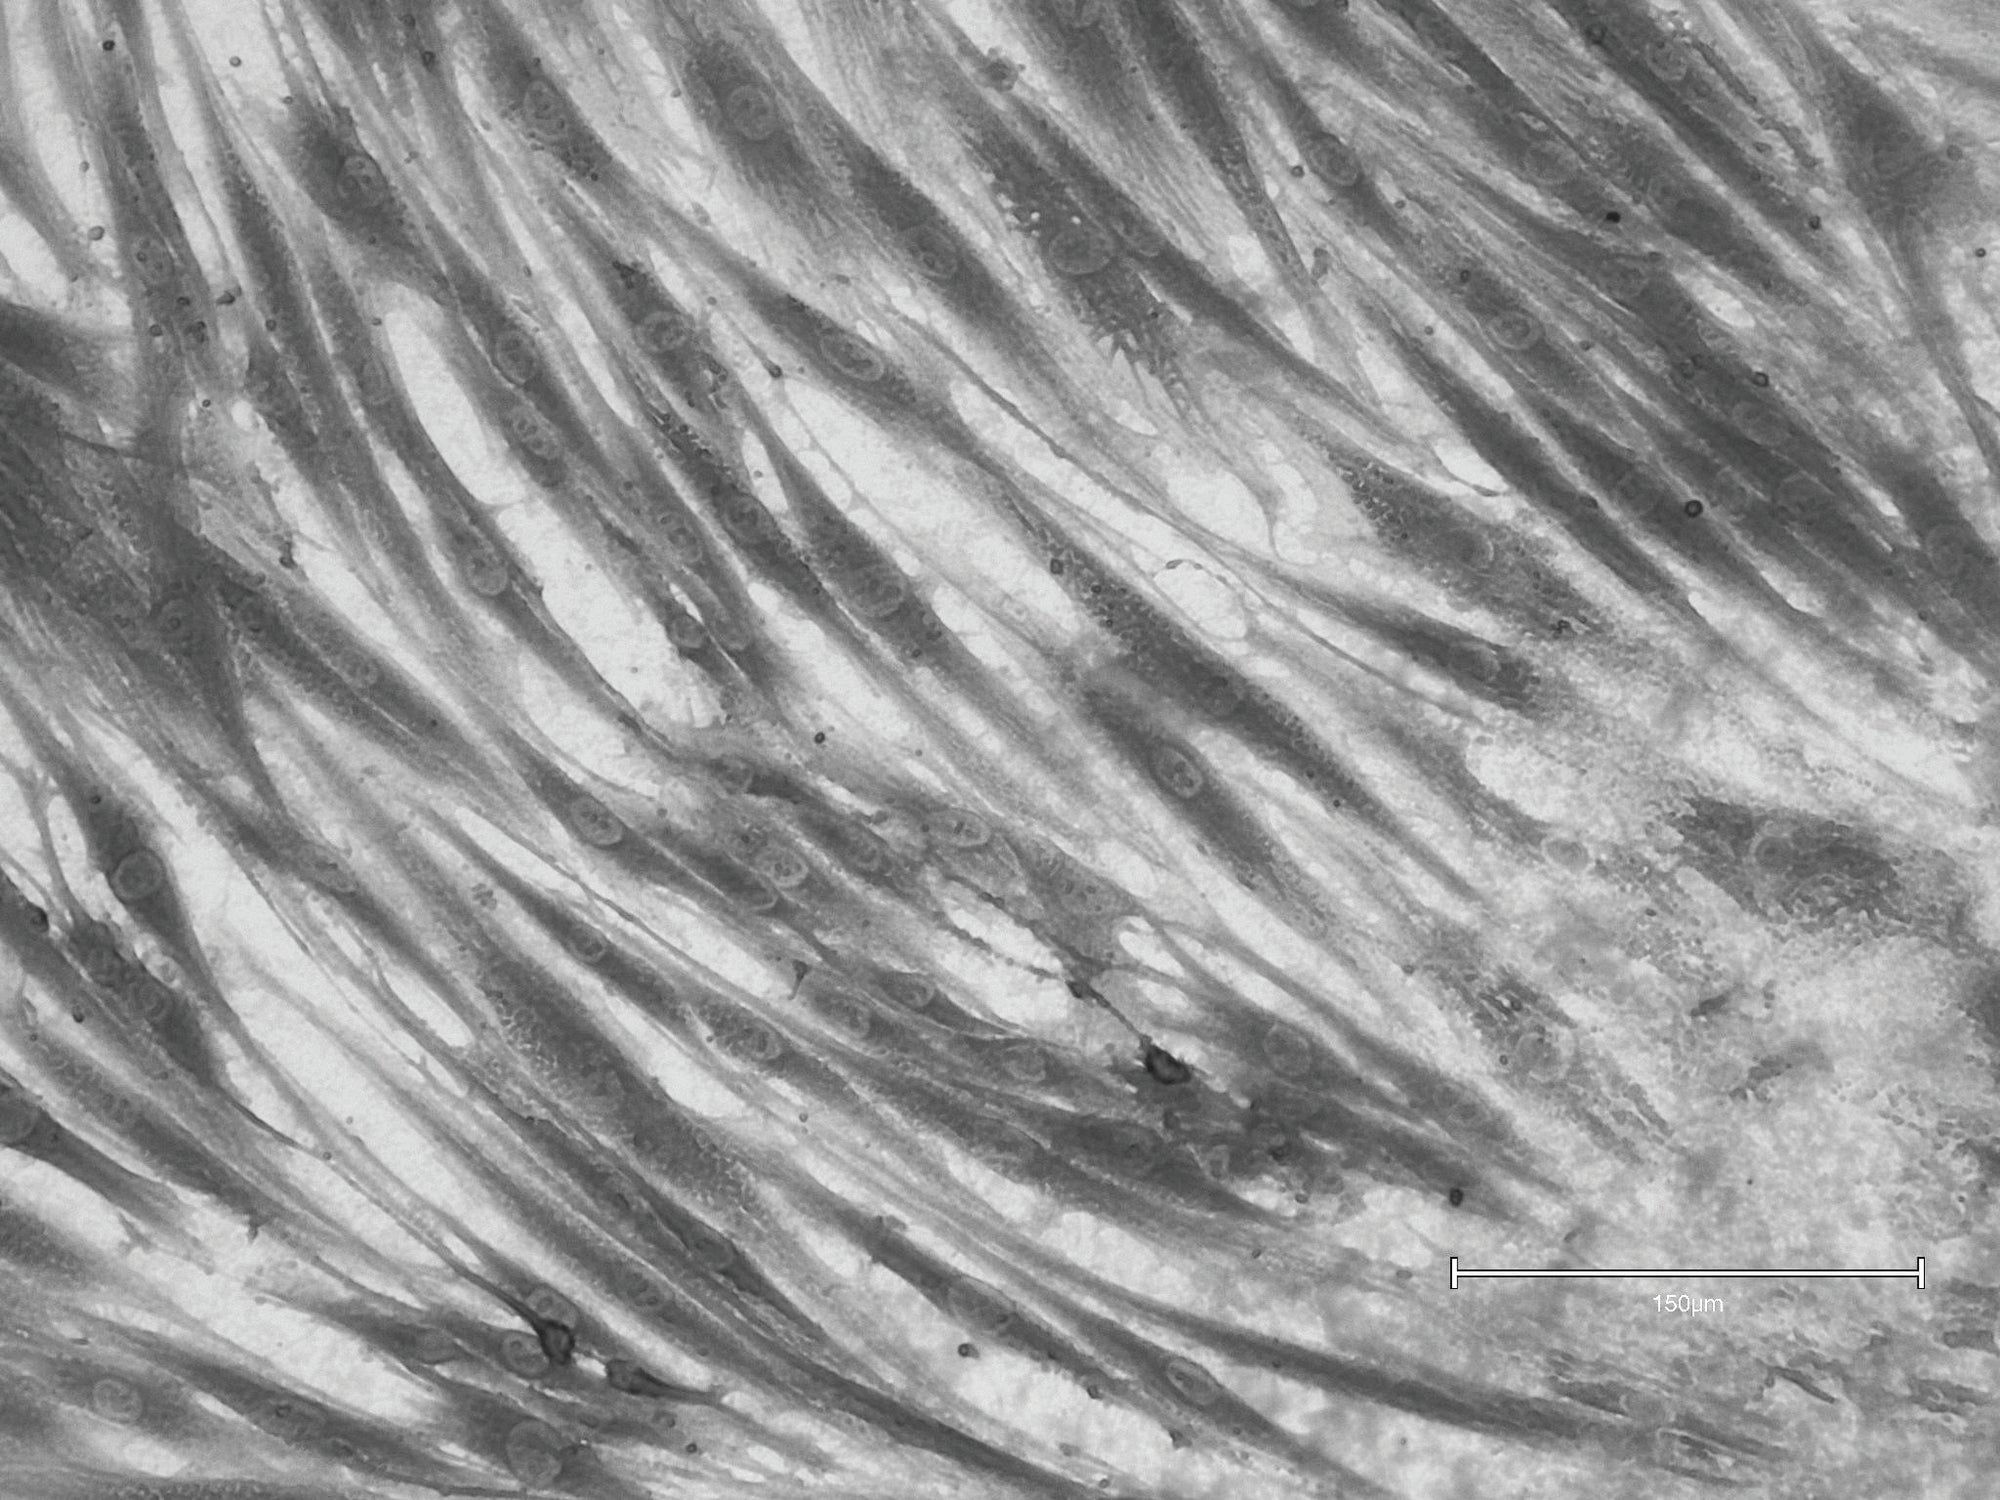

No Treatment (Control)